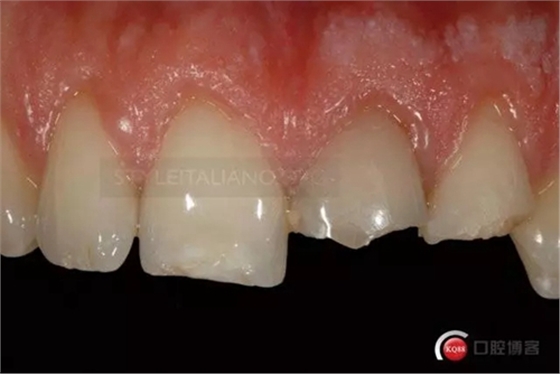

Until the immediate final outcome

Control one month check shows a natural smile